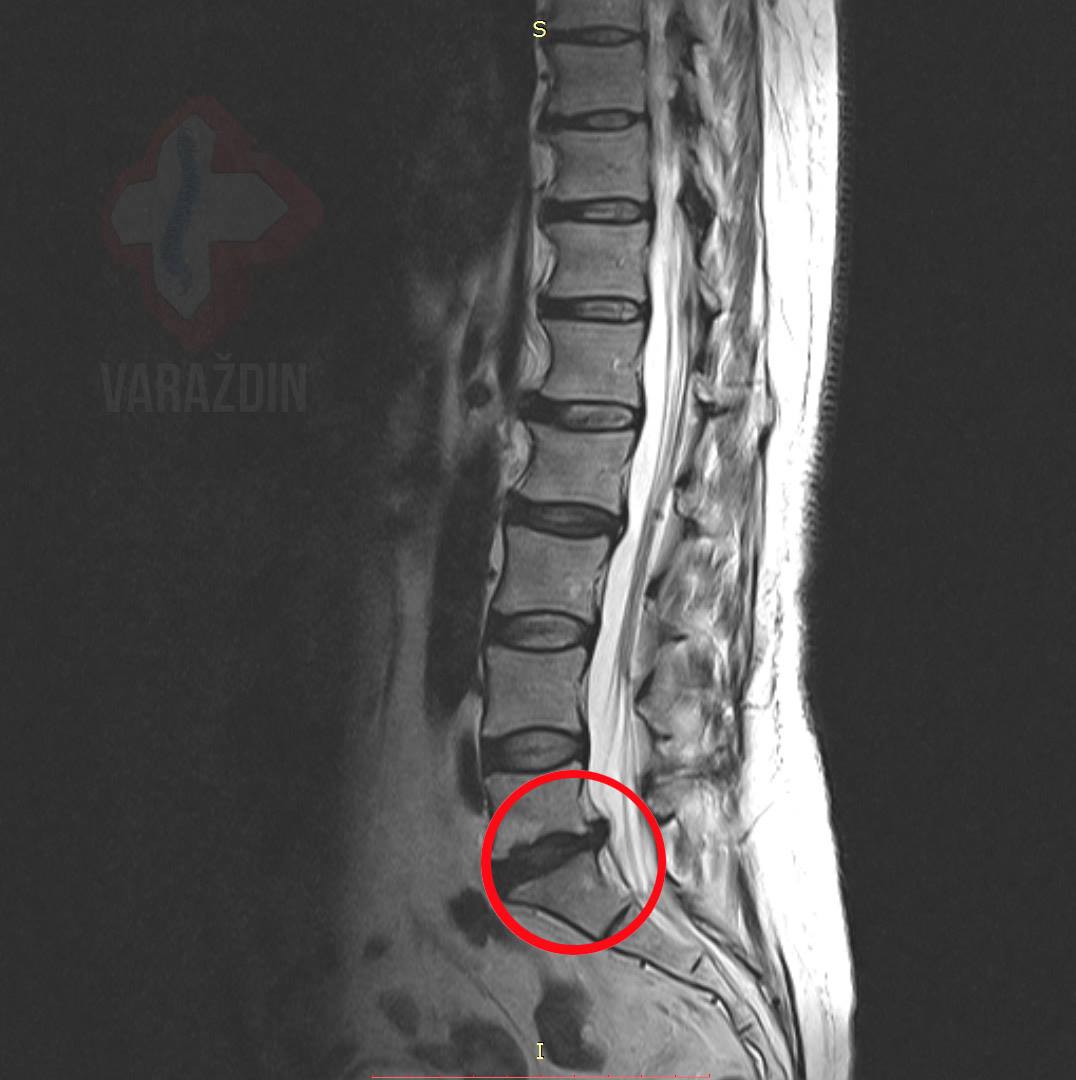

Klijent se javlja u Nado centar sa snimkom na kojoj je

vidljiva sekvestacija diska. Kod klijenta je prisutna bol u

križima preko lijevog gluteusa duž lijeve noge uz lagane trnce u

potkoljenici. Nakon konzultacija i utvrđenog optimalnog tijeka

liječenja, klijentu se kroz 15 dekompresijskih

tretmana sekvestar razgradio.